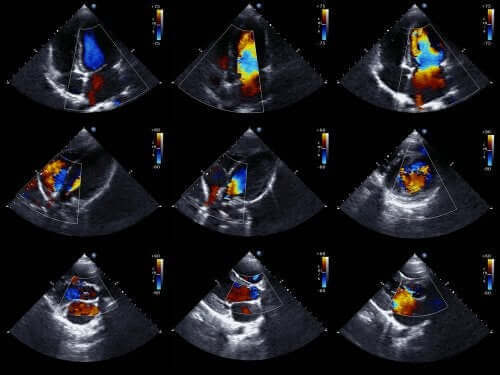

通常、赤ちゃんが産まれる前に、心臓超音波検査を行うことによってこの疾患を診断することができます。これは超音波を使用して動いている心臓の画像を再現する技術です。

これにより、赤ちゃんが子宮内にいるときに心臓を確認することができ、心臓の機能を検査することができるのです。この情報をもとに、赤ちゃんが産まれてすぐに治療が行われます。